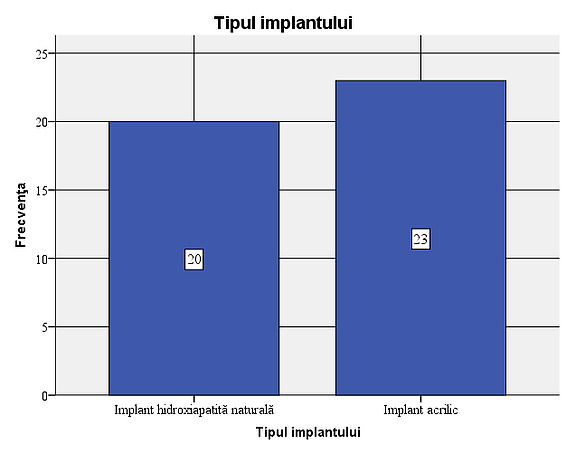

Figure 8: Age variation within the sample:, it is found that their average age is 57.42. The age deviates from the average by plus or minus 5.36 years. The acrylic implant was used in 23 of the patients studied (53.5%), while the natural hydroxyapatite implant was used in 20 of the patients (46.5%).

Figure 9: Type of implants used in the sample: 23 of the patients studied (53.5%) had a non-integrated acrylic implant (PMMA), while the natural hydroxyapatite implant was used in 20 of the patients (46.5%).